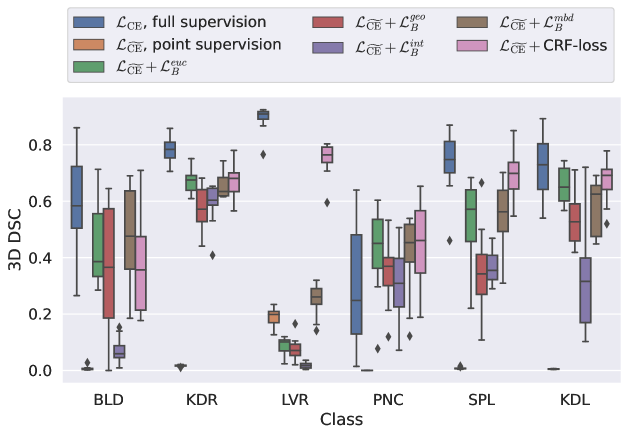

5.1 Segmentation of cardiac structures

The average 3D Dice scores and HD95 values on the ACDC test set are given in Table 2, and boxplots in figures 4 and 5 show the distributions. We see that, in terms of DSC, the proposed strategy of using intensity-aware distances withing boundary loss performs better than simply using the Euclidean distance, with the best results achieved by using the strictly intensity based MBD. The HD95 however favors the original version of , which may be do to its smoother predictions and less fragmentation and oversegmentation. The CRF-loss results are significantly worse in both metrics.

In Figure 6 we provide qualitative results on a number of randomly chosen test set slices. Upon visual inspection, we can observe that training with the intensity-aware distances (particularly with and ) follows the image gradients better and is better at recovering the underlying shape than the Euclidean version. The CRF-loss seems to recover the shape of the myocardium and left ventricle to some extent, but fails entirely on the right ventricle.

5.2 Abdominal organ segmentation

In Table 3, the average DSC and HD95 results are shown (both using 2D and 3D distance maps) for the task of abdominal organ segmentation in POEM data (for boxplots see figures 8 and 9). We see that training with and (with distances calculated on 2D slices) performs comparably, while using and produces lower scores in both DSC and HD95 metric. On this dataset, the CRF-loss is able to compete with the boundary loss-based training strategies, even outperforming them on most classes. Most notably, all models trained with boundary loss appear to have a hard time segmenting the liver. We hypothesize this may be due to extremely severe class imbalance, as the liver covers a very large area compared to the rest of the classes. It is thus also more strongly affected by undersegmentations.